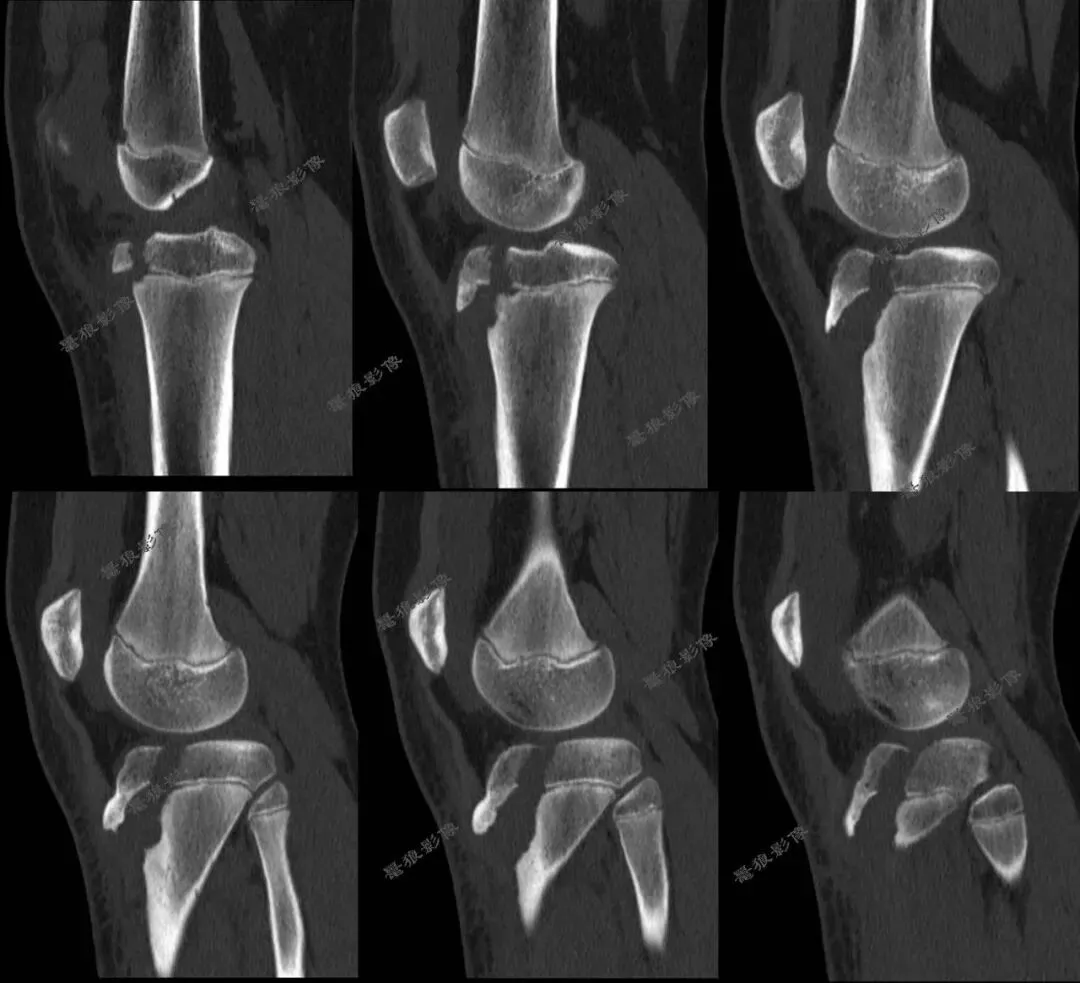

D、胫骨结节骨折病例分享

M,11y。

缘患者入院3小时余前运动后出现左膝部疼痛,活动受限,当时无昏迷,遂送至急诊就诊,查X片:左胫骨结节骺离骨折。

二.术前CT

胫骨结节骨折(OgdenIIIA型 )

一.任一提示 Ogden II型 及以上的骨折,应高度警惕骨折累及关节内延伸与后方干骺端成分,推荐CT进行三维重建和软组织评估,必要时联合MR检查。

二.胫骨结节骨折以骨折线走行、骺板及关节面受累情况,以及骨折移位、粉碎程度为核心,直接关联是否需要手术、术式复杂度和并发症风险。